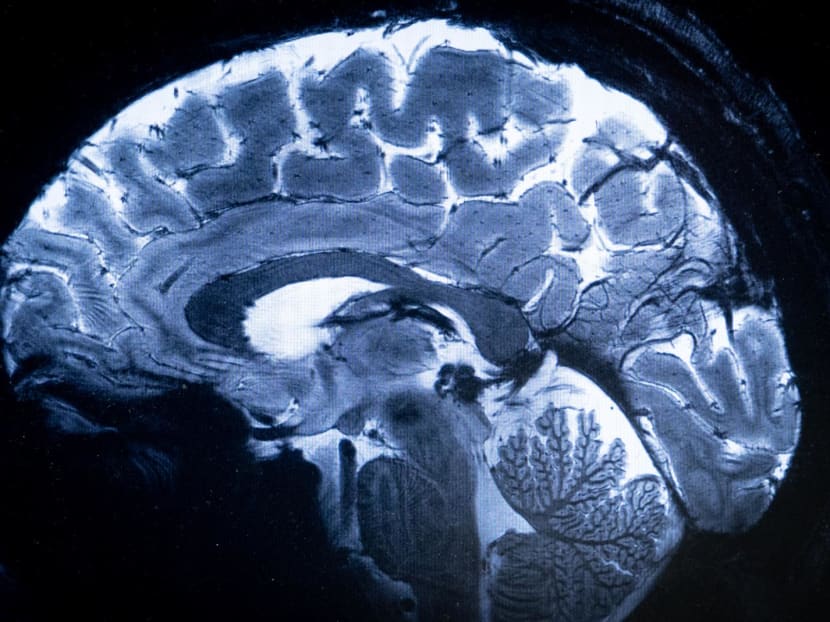

World's most powerful MRI scans first images of human brain

SACLAY (France) — The world's most powerful magnetic resonance imaging (MRI) scanner has delivered its first images of human brains, reaching a new level of precision that is hoped will shed more light on our mysterious minds — and the illnesses that haunt them.

"We have seen a level of precision never reached before at CEA," said Mr Alexandre Vignaud, a physicist working on the project.

This power allows the machine to scan images with 10 times more precision than the MRIs commonly used in hospitals, whose power does not normally exceed three teslas.

On a computer screen, Mr Vignaud compared images taken by this mighty scanner, dubbed Iseult, with those from a normal MRI.

"With this machine, we can see the tiny vessels which feed the cerebral cortex, or details of the cerebellum which were almost invisible until now," he said.